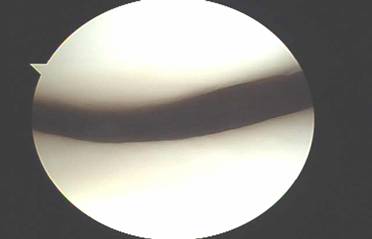

The cartilage surfaces behind the kneecap are the thickest in the entire human body and usually begin to wear out after the age of 15. Almost all people have evidence of cartilage damage on kneecap cartilage when we perform arthroscopic surgery. It is interesting to note however that while the pain from chondromalacia is the most common complaint of people between the ages of 15 and 60, these complaints usually disappear after age of 60. In addition, most persons with chondromalacia do not have symptoms.

When exercises fail to improve the knee then surgery may be indicated if the symptoms are significant enough to alter activities. The most common arthroscopic surgical procedures to treat chondromalacia include chondroplasty and microfracture / abrasion procedure. A chondroplasty involves smoothing out roughened surface cartilage which can decrease friction forces on the surface cartilage and decrease symptoms of chondromalacia. An abrasion or microfracture is most useful when there is a small contained area of exposed bone or complete loss of surface cartilage. During this procedure the bone is tapped with a pick-type tool which causes bleeding in the area of exposed bone. This blood from deep inside the bone carries stem cells which can cause the bone to grow a scar type cartilage. This scar cartilage has been shown to be very effective in reducing knee pain in several orthopedic studies.